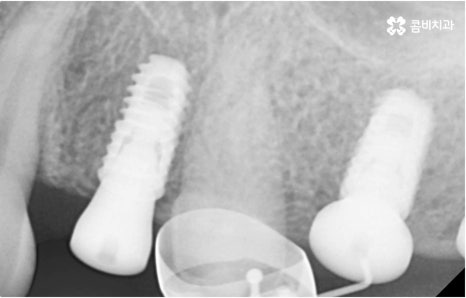

임플란트는 유치, 영구치 이후로 제 3의 치아라고 불리울 만큼 자연 치아의 상실에 대처하는 인공 치아 중에 가장 각광을 받고 있습니다. 저작력 회복이 80%에 가깝고 심미적으로 자신의 치아와 거의 다름없어 보이는 부분에서도 만족도가 높아 많은 분들이 찾고 있지만 식립 성공률과 안정적인 지속률에 크게 영향을 주는 올바른 위치 및 각도로의 식립을 무리하지 않게 진행하기 위해 술자의 높은 숙련도를 요하는 고난도의 수술이기 때문에 임상 경험이 많고 뛰어난 노하우를 갖추고 있는 담당의 선생님과 함께 하시는 것이 중요한 포인트라고 할 수 있어요.

환자분들의 상황에 따라 하루 만에 식립 및 임시 치아 장착까지 끝나서 바로 식사를 할 수 있는 원데이 임플란트 과정, 정밀 검사 후 디지털 장비를 이용하여 모의 수술 후 맞춤 가이드를 따라 무절개 / 최소절개 수술을 진행하는 네비게이션 임플란트 과정 등 관련 기술이 점점 더 섬세하게 발달하고 있어서 보다 편안한 이용이 가능하게 된 것은 사실이지만 본래 자신의 치아보다 좋은 인공 치아는 없을 것이기 때문에 건강할 때 이를 잘 유지 관리하고 구강 질환이 발생했을 때는 되도록 빠르게 이에 대처하실 필요가 있어요.